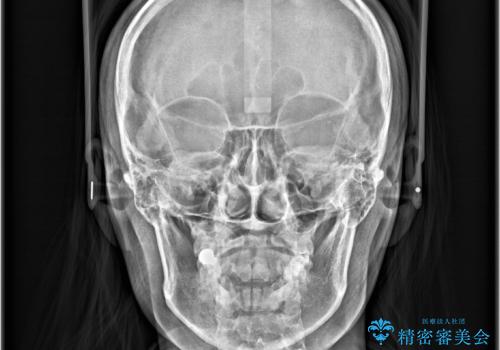

- 歯の捻じれやデコボコを主訴にご来院された患者様です。

矯正治療の精密検査を行った結果、非抜歯(歯を抜かない)矯正治療を選択いたしました。

本症例では、治療の途中で**バイトアップ(咬み合わせを一時的に挙上する処置)**を行い、

上下の歯が干渉しない環境を作りながら、捻転や叢生の改善を進めました。